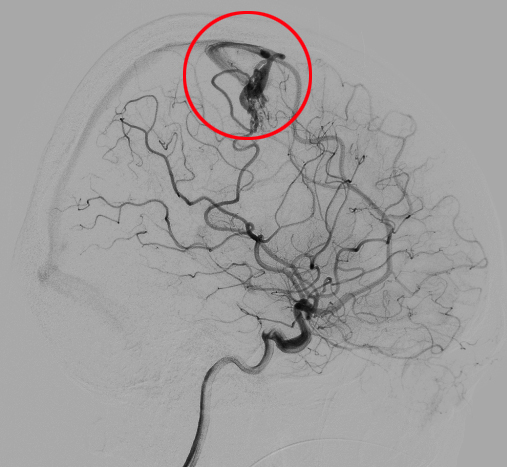

得益于潞河医院复合手术室的先进配置,血管造影检查和外科手术无缝衔接。经脑血管造影确诊为脑血管畸形。医生们面对患者出血部位在大脑重要功能区的复杂情况深知手术难度巨大,但家属给予的充分信任让大家坚定了信念。王长江和胡艳龙副主任医师通过三维重建技术精准定位血管畸形的供血动脉,在麻醉科和手术室医护人员的紧密配合下,复合手术开始了。血管造影精准定位责任血管,介入医生应用栓塞技术栓塞部分高危出血动脉,张洪兵主任在手术显微镜下仔细清除血肿、切除畸形血管团,每一步都需要高度专注和精湛技艺。术中还采用实时电生理监测技术,确保语言和运动功能不受影响。经过七个多个小时的奋战,手术顺利结束。

脑血管畸形

脑血管畸形是脑血管先天性、非肿瘤性发育异常。正常脑血管分布有序,而脑血管畸形时,局部脑血管结构和数量异常,常见如动静脉畸形等。畸形血管易破裂出血,引发剧烈头痛、呕吐、意识障碍等,严重威胁生命,还可能导致癫痫发作、脑缺血等症状。头部CT、核磁及脑血管造影等可明确诊断。治疗方式根据具体情况,包括手术切除、血管内介入治疗、放射治疗等。若发现相关症状,应及时就医排查,早发现早治疗。